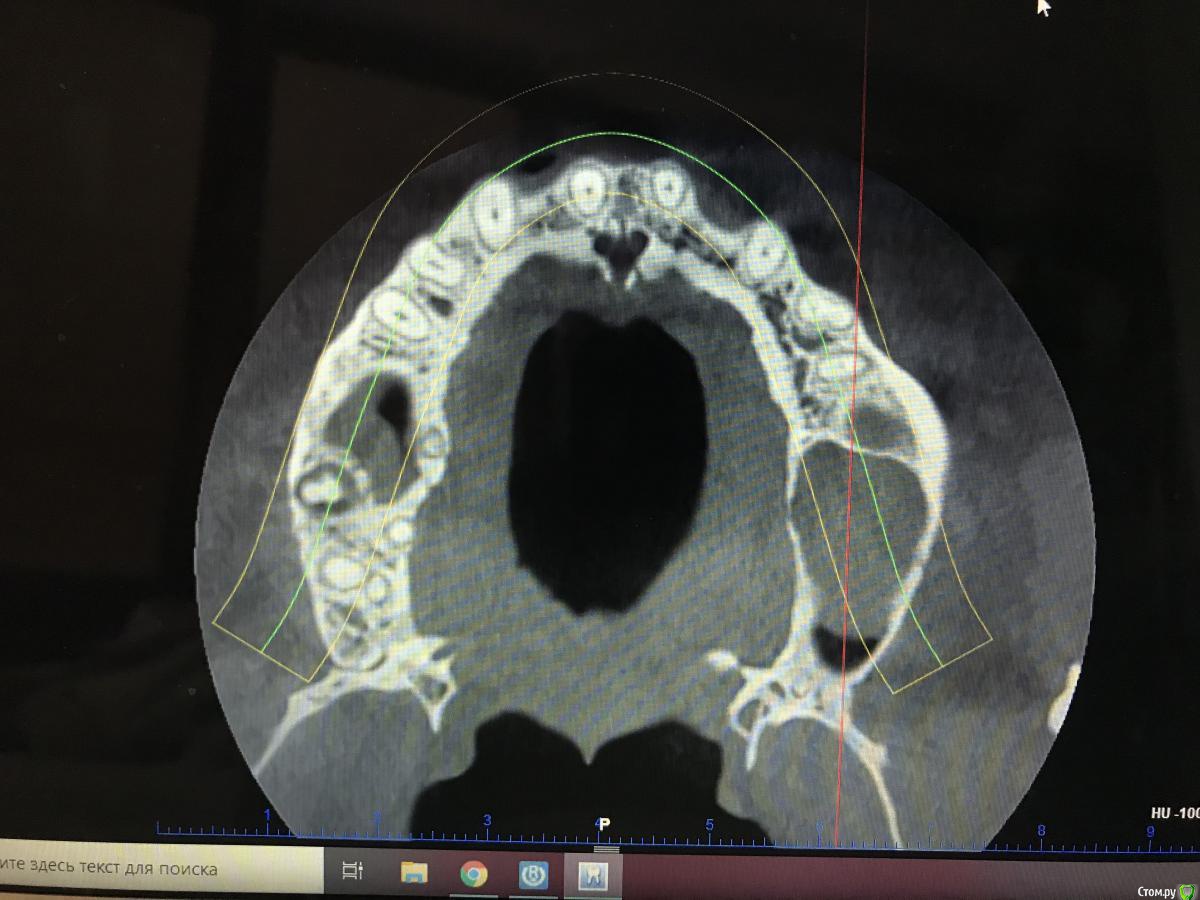

колесников Опубликовано 5 августа, 2020 Поделиться Опубликовано 5 августа, 2020 Вообще не трогайте. Вы что Д’Артаньян ? Очень толстая стенка синуса,сделайте закрытый синус. Киста или сама лопнет или пациент к Лору обратится если что то забеспокоит. Качество кости не смущает? Что за пациент? Как выглядит костная ткань на н/ч? Эмаль не изменена? Сопутствующие патологии имеются? Ссылка на комментарий

Kilgen Опубликовано 24 августа, 2020 Поделиться Опубликовано 24 августа, 2020 Закрытый с.л + т.л 6 мм Ссылка на комментарий

Александр07 Опубликовано 30 августа, 2020 Поделиться Опубликовано 30 августа, 2020 Неплохое кт, это планмека? Либо 4 мм имплант тишью левел, не затрагивая гайморову, либо открытый синус с croco eye.Если мануал высокий и уверенность и опыт есть в закрытии перфорации то пошёл бы по ядаху но там высокий риск образования большой перфы, поэтому хорошая альтернатива это короткие широкие импл и закрытый с л Ссылка на комментарий

Александр07 Опубликовано 30 августа, 2020 Поделиться Опубликовано 30 августа, 2020 Ну или по классике лор санация и осл со стандартными импл Ссылка на комментарий